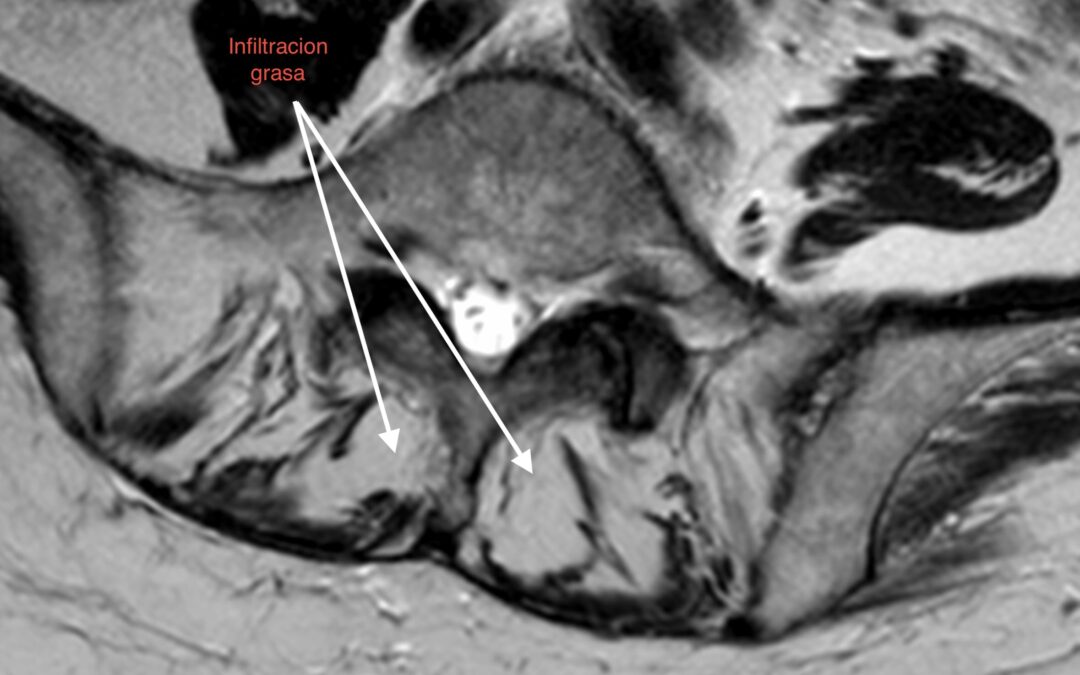

1. Pérdida del «Tirante» Dinámico: Los músculos multífidos actúan como estabilizadores segmentarios finos. En pacientes sarcopénicos, estos músculos son reemplazados por tejido adiposo no contráctil, perdiendo su capacidad de tensión.

• Calidad vs. Cantidad: La infiltración grasa (clasificación de Goutallier o medición de unidades Hounsfield en TAC) en el multífido es un factor de riesgo independiente para la reintervención. Músculos con alta infiltración grasa se correlacionan con peores resultados funcionales (ODI) y mayor tasa de complicaciones mecánicas como la cifosis de la unión proximal (PJK).

1. Screening Preoperatorio Rutinario: La RM lumbar debe utilizarse para evaluar la calidad muscular (corte axial en L3/L4), no solo la patología neural.